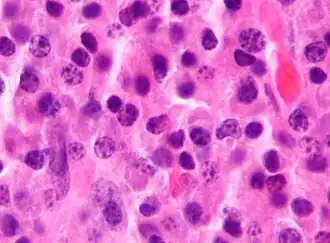

Micrograph of a plasma cell with distinct clear perinuclear region of the cytoplasm, which contains large numbers of Golgi bodies.

Plasma cells are large lymphocytes with abundant cytoplasm and a characteristic appearance on light microscopy. They have basophilic cytoplasm and an eccentric nucleus with heterochromatin in a characteristic cartwheel or clock face arrangement. Their cytoplasm also contains a pale zone that on electron microscopy contains an extensive Golgi apparatus and centrioles. Abundant rough endoplasmic reticulum combined with a well-developed Golgi apparatus makes plasma cells well-suited for secreting immunoglobulins.[4] Other organelles in a plasma cell include ribosomes, lysosomes, mitochondria, and the plasma membrane.